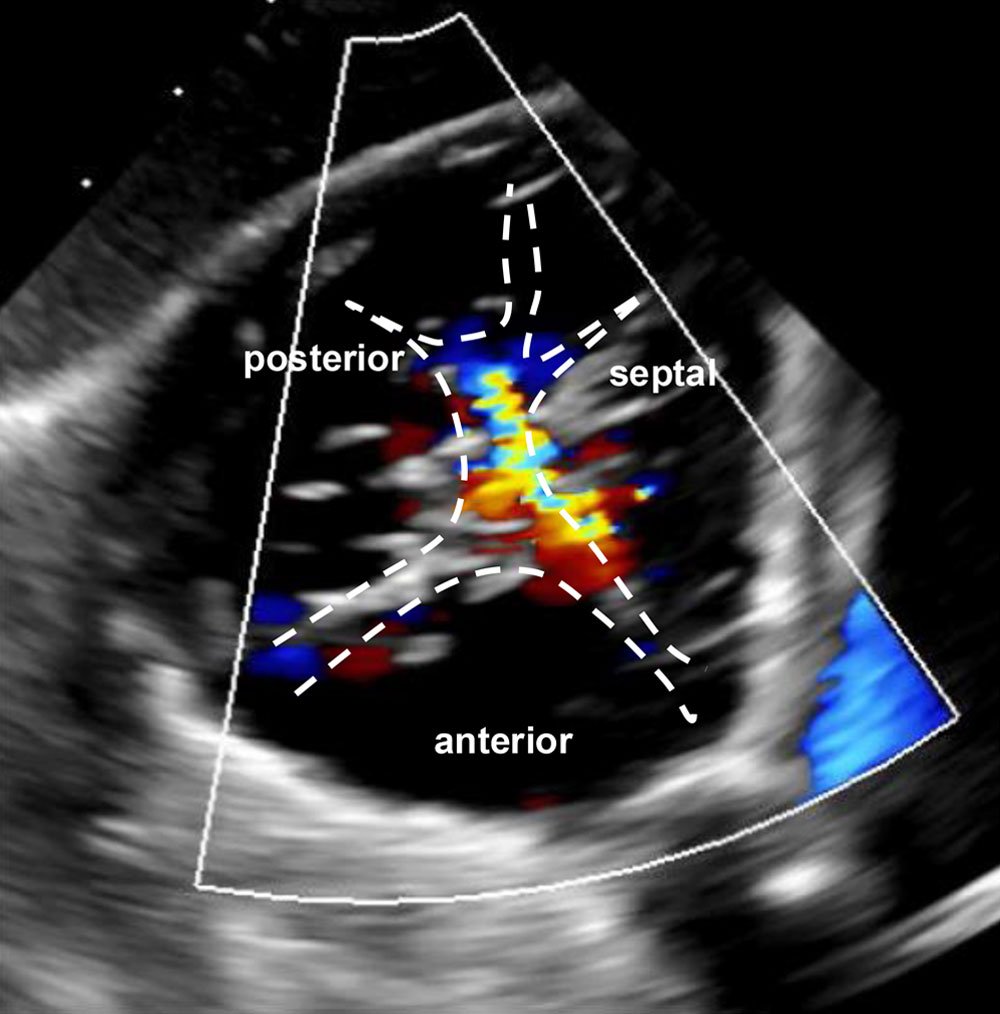

Echocardiographic assessment

Transgastric leaflets

The Heart Team further discussed tricuspid anatomy derived from echocardiography as shown above and qualified according to Hausleiter J et al. (JACC 2025) in the feasible anatomy for T-TEER group, according to the following case criteria:

- Torrential functional TR with septolateral coaptation gap ≤ 7 mm

- Regurgitant jets: anteroseptal and posteroseptal

- Leaflet morphology: suitable with identifiable segmentations of posterior and septal leaflets

- No CIED leads present

- Echocardiographic visualisation: adequate